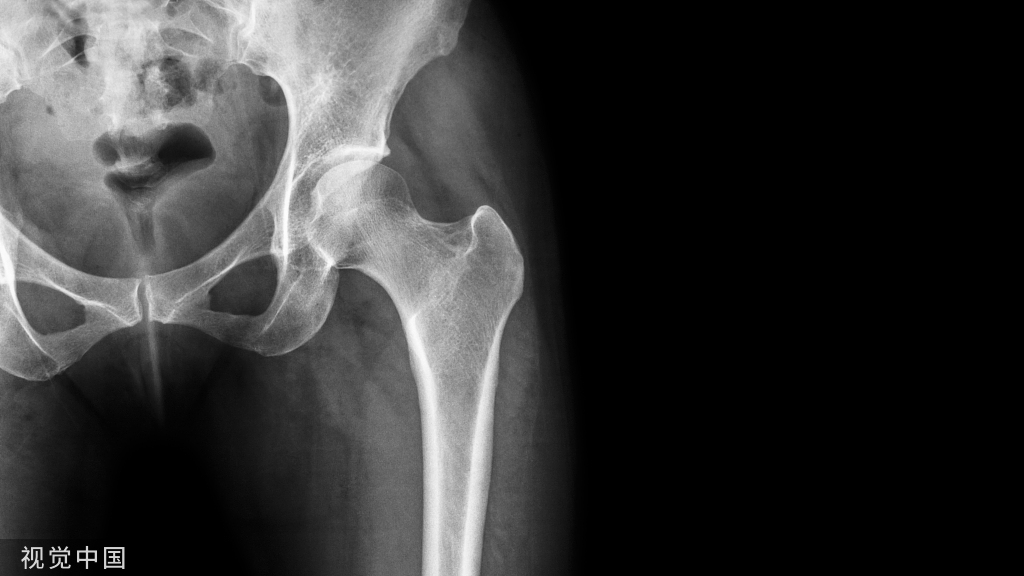

骨性关节炎(OA)又称退行性骨关节病,是一种由于关节软骨退行性变,引起的关节软骨完整性破坏及关节边缘软骨下骨板病变,继而导致关节症状和体征的一组慢性退行性关节疾病。易受累关节有膝关节、髋关节、脊柱、手等,其中膝关节炎占41%。